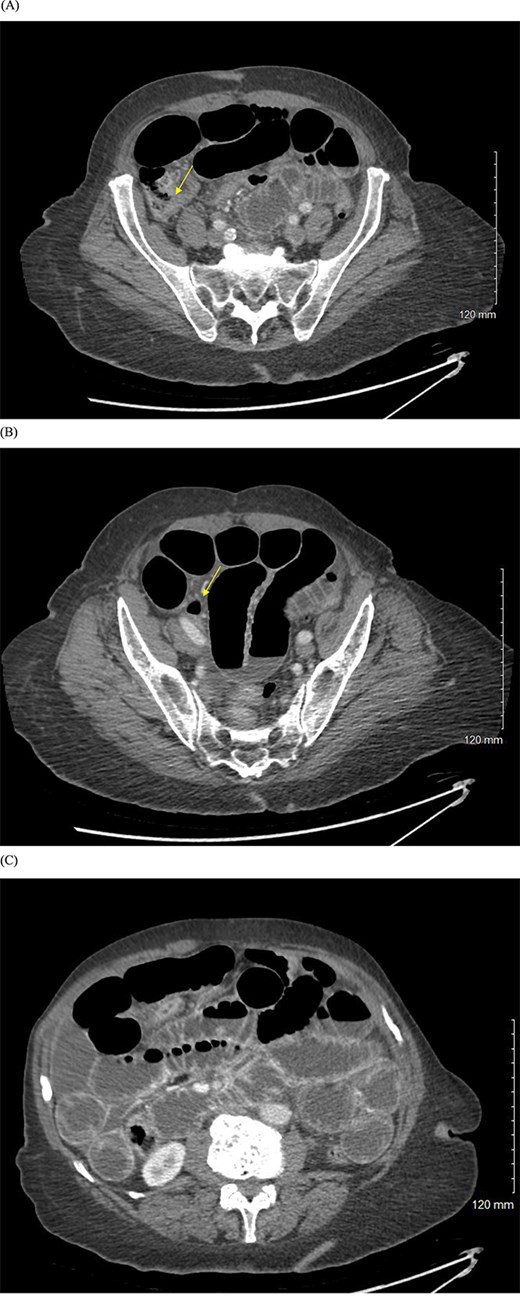

CT abdomen and pelvis scan demonstrated dilated loops of small bowel with a likely closed-loop component as seen in Fig. 1. Imaging also showed a large hiatal hernia with significant gastric distension. Surgery was consulted and the patient was taken to the operating room expeditiously.

(A, B) CT abdomen and pelvis with IV contrast showing evidence of small bowel obstruction with two transition points in the right lower quadrant (yellow arrows). (C) Dilated loops of small bowel with air-fluid levels.